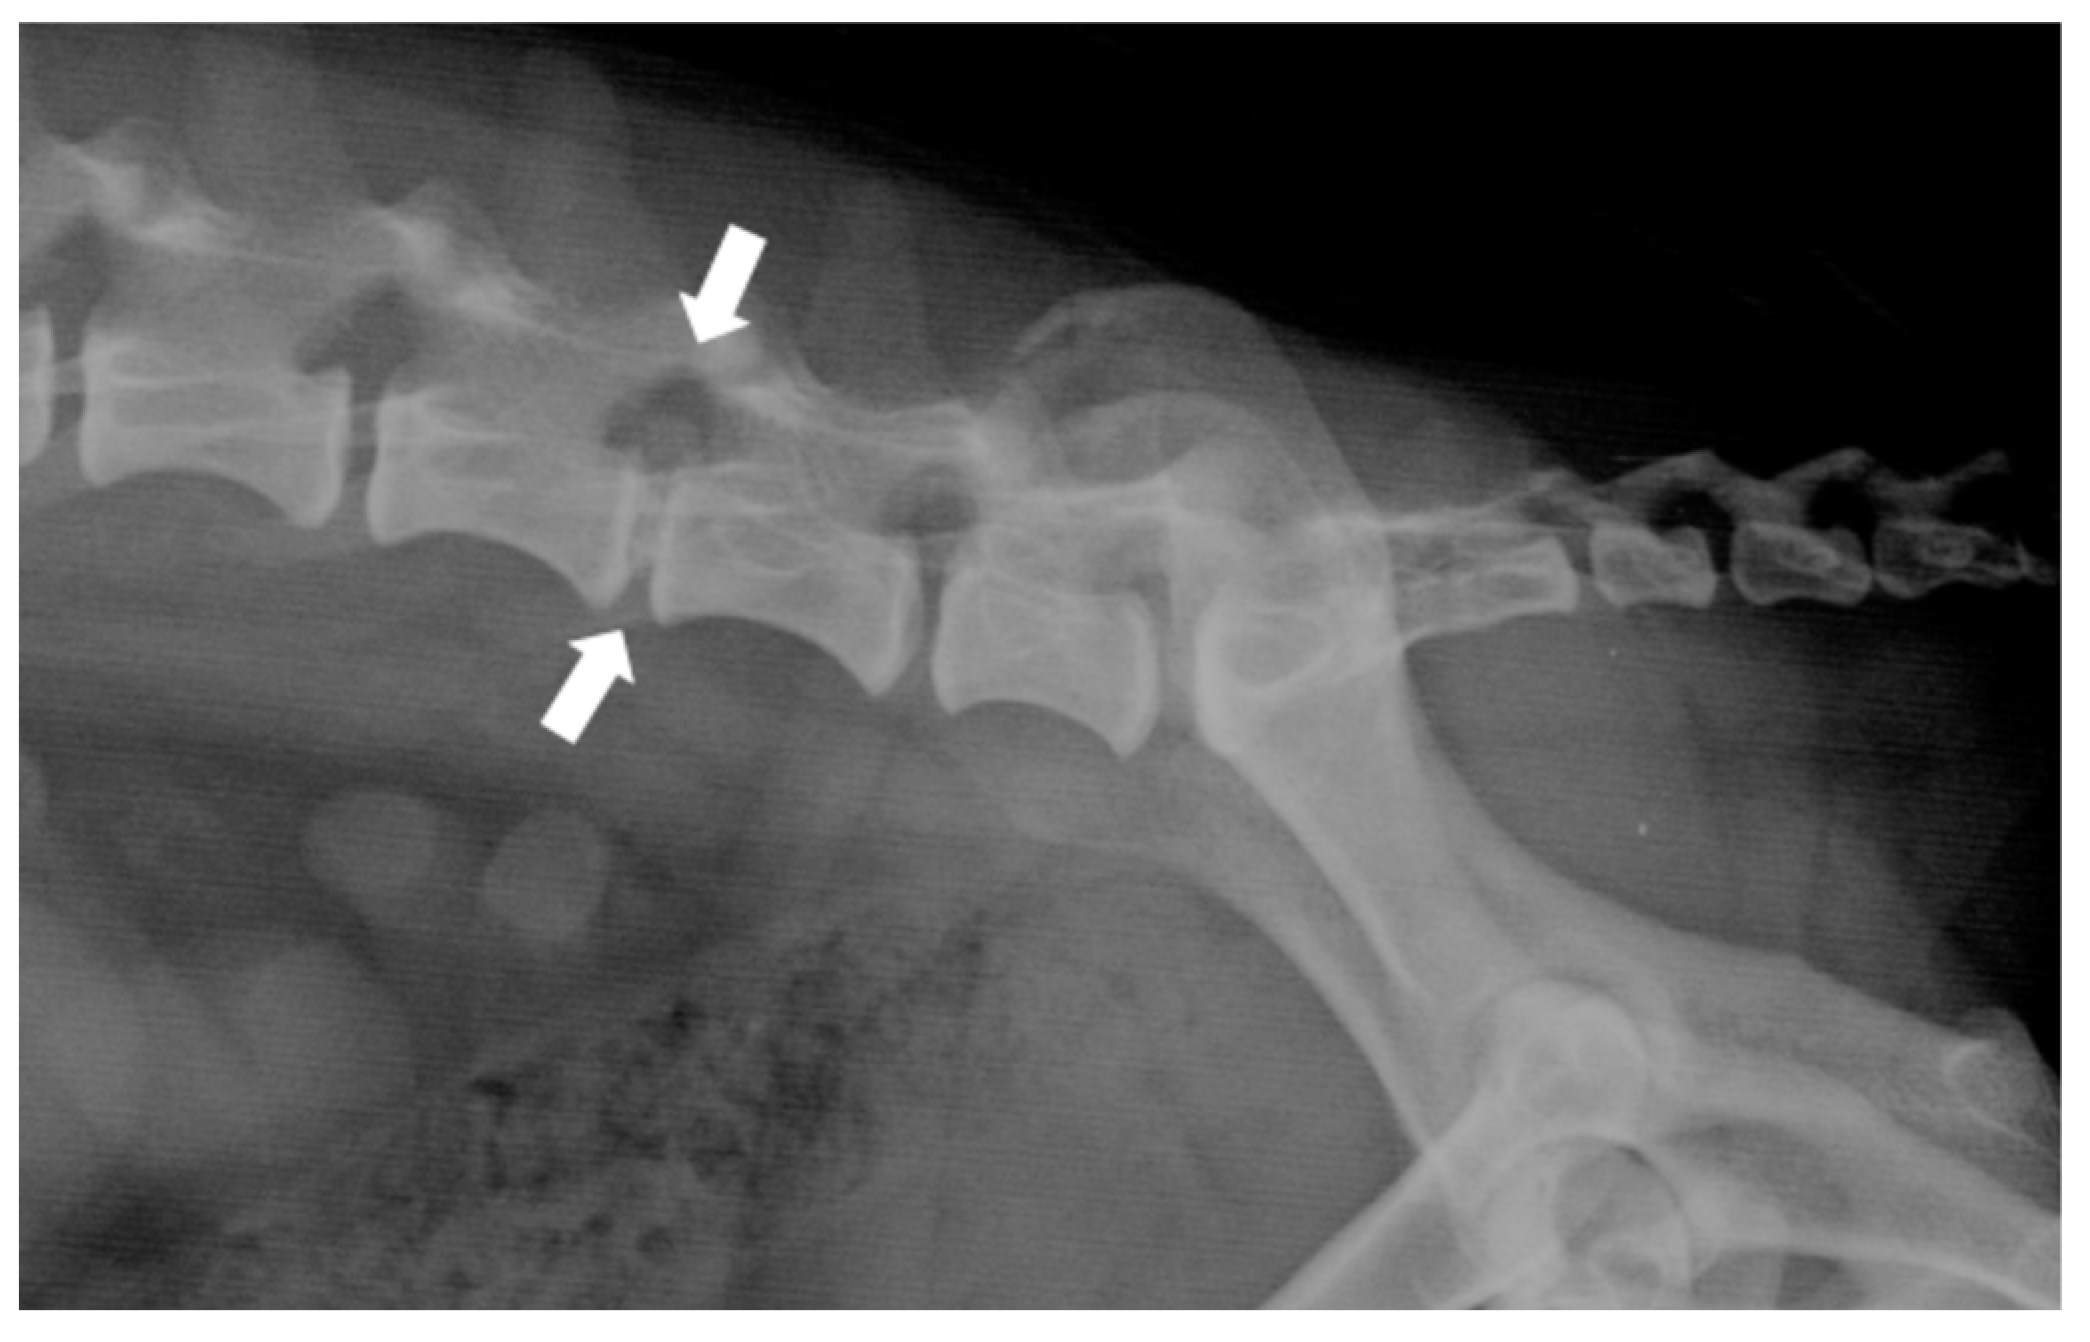

Plain radiographs (Figure 3) are a commonly used tool in the veterinary clinic, although they show notable limitations in the evaluation of disc extrusions. Radiographic findings associated with extrusions include reduction of the IVD space, narrowing of the facet joints, opacity of the intervertebral foramen, presence of mineralized disc material in the vertebral canal, and vacuum phenomena. Although radiographs achieve an accuracy of between 51% and 94.7% in the identification of the herniated disc space, they do not provide sufficient information on the extent of extrusion, lateralization, nor the degree of spinal cord compression. Therefore, they are not suitable as an exclusive diagnostic tool, and their usefulness is limited to ruling out other spinal diseases [38].

Figure 3.

Right-lateral radiograph of the lumbosacral spine of a dog with a surgically confirmed disc extrusion at L5-L6 (white arrow). Note the reduction of the intervertebral disc space and the presence of mineralized disc material in the vertebral canal.